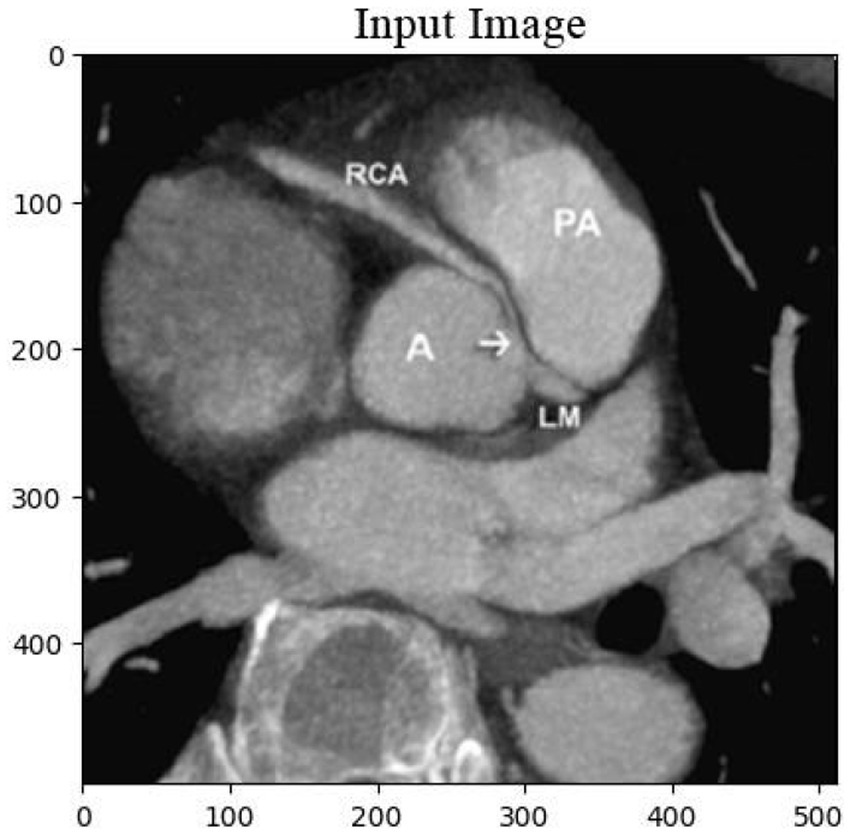

The cardiac CT Input Image is shown in Figure 4. In the preprocessing stage of cardiac CT image analysis, the initial step involves resizing the input images to a standardized dimension of 64 pixels by 64 pixels. This resizing procedure is crucial to establishing a uniform and manageable input size for subsequent analysis. Standardizing the image dimensions not only aids in computational efficiency but also ensures consistency in the input data fed into the analytical models. A 64 by 64-pixel resolution is likely driven by a balance between maintaining sufficient image detail for meaningful analysis and minimizing computational resource requirements. By establishing this standardized input size, the subsequent stages of image processing and feature extraction can be conducted with a consistent and optimized foundation, facilitating robust and reliable cardiac CT image analysis. Resized Input Image is shown in Figure 5.

Figure 4

Original cardiac CT image before preprocessing, used as the input for the analysis pipeline. This image undergoes resizing to standardize dimensions for effectual and consistent processing.